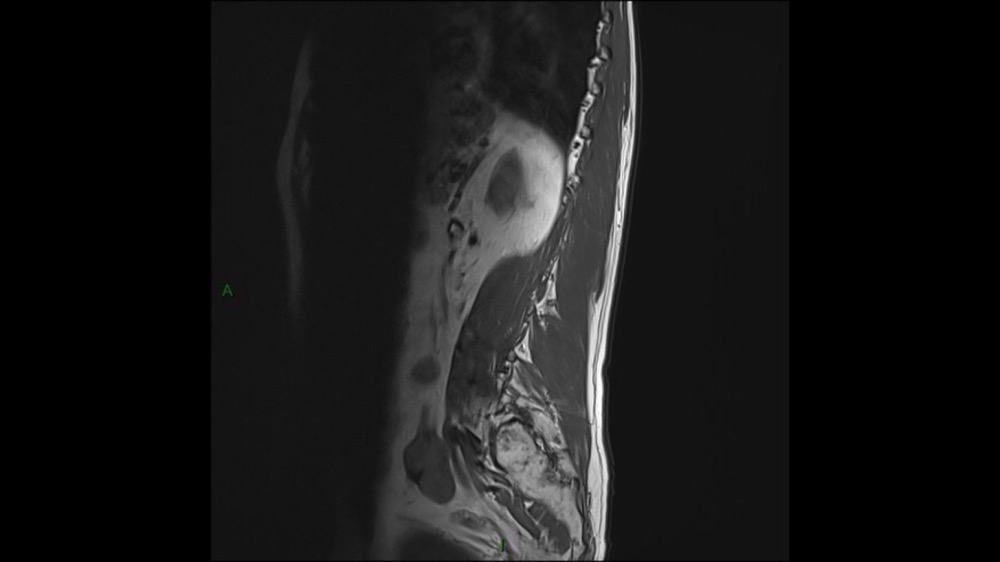

Lombo-cruralgie subaiguë trompeuse

Pascalie Jallerat 22/06/2020